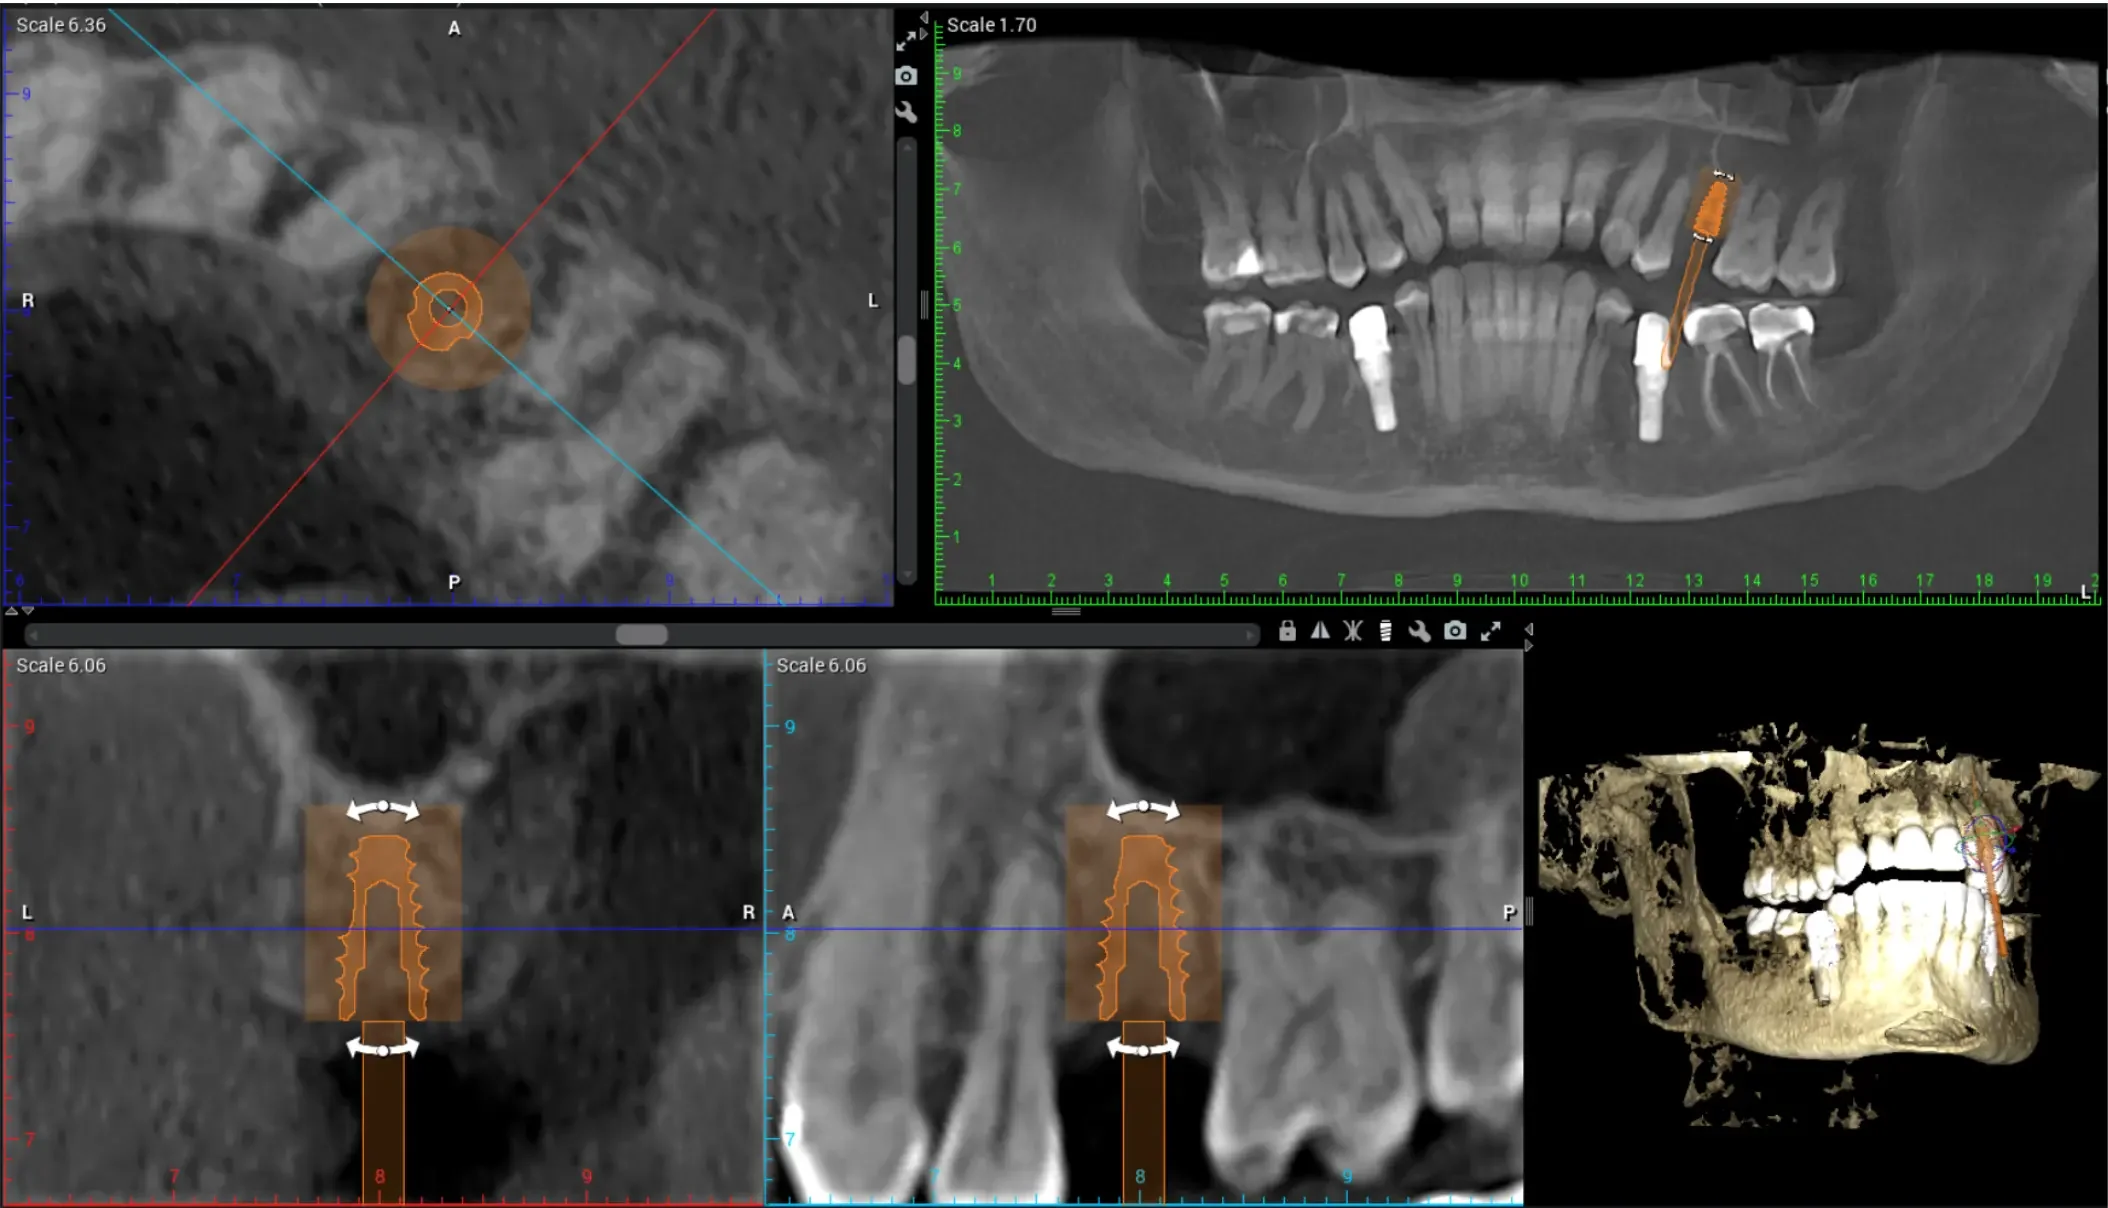

Our team combines advanced imaging, precise anesthesia techniques, sedation, and years of surgical experience to ensure your procedure is gentle, efficient, and stress-free.

A real patient example: the tooth from above was extracted and a bone graft was placed. This is not always needed!

To preserve your bone and your smile, most patients choose a socket preservation bone graft immediately after extraction.

UPGRADE: Bone Grafting makes future implant placement far more predictable — and prevents the “sunken” look that can occur when bone resorbs.